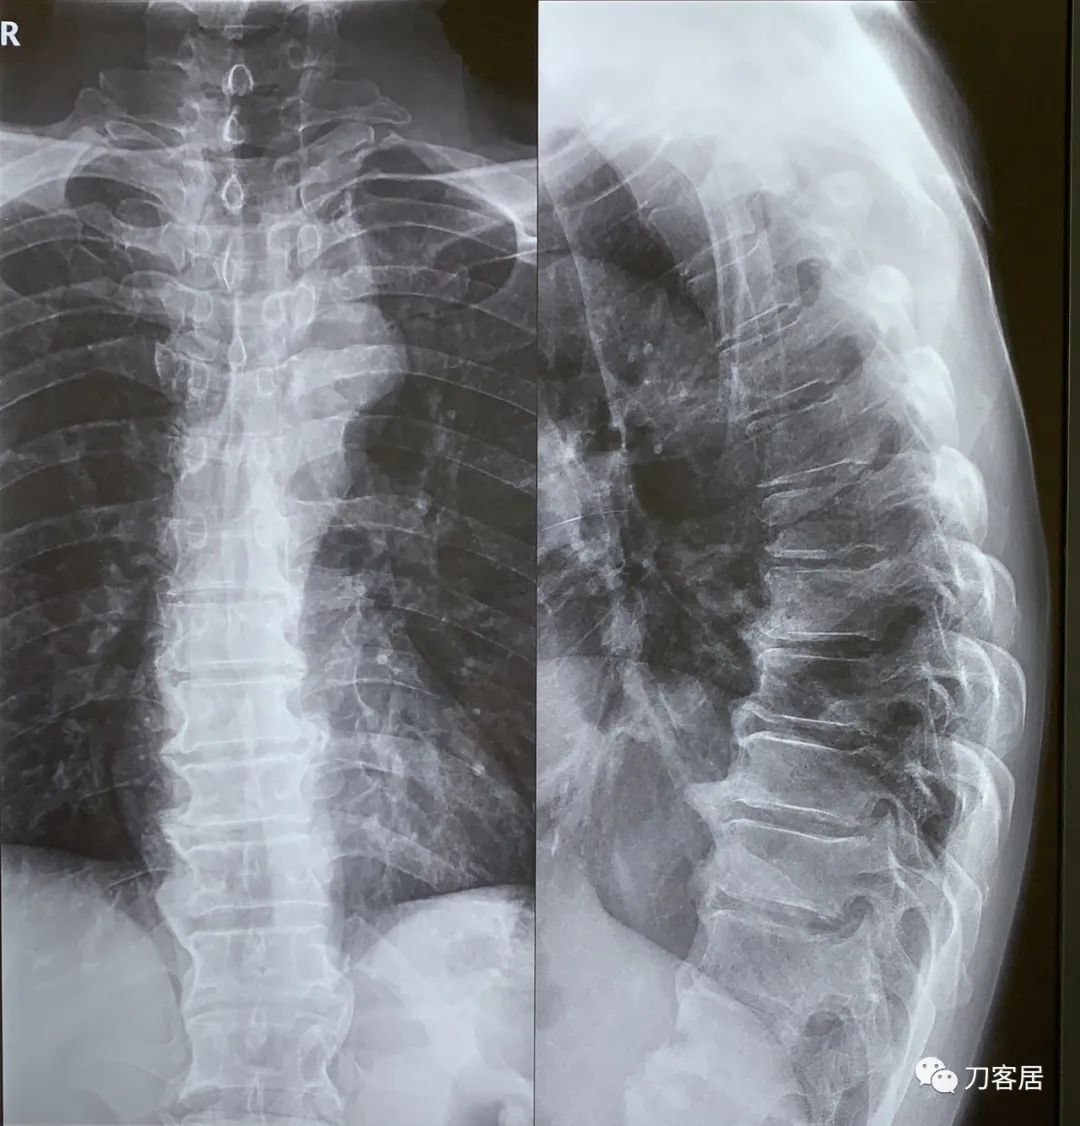

图1. 20210621西京医院腰椎正侧位X线片

图10. 20210622西京医院胸椎正侧位X线片